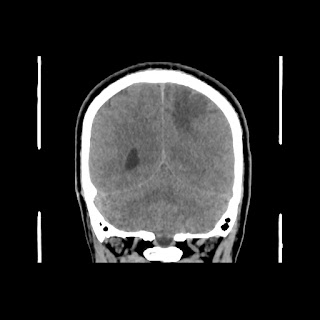

A 35 years old man CT head